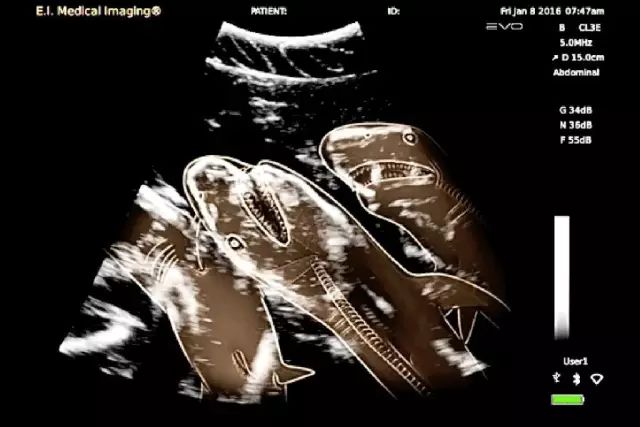

4. 鲨鱼。

这也太恐怖了吧…有种说法就是鲨鱼在母亲的肚子里就开始自相残杀